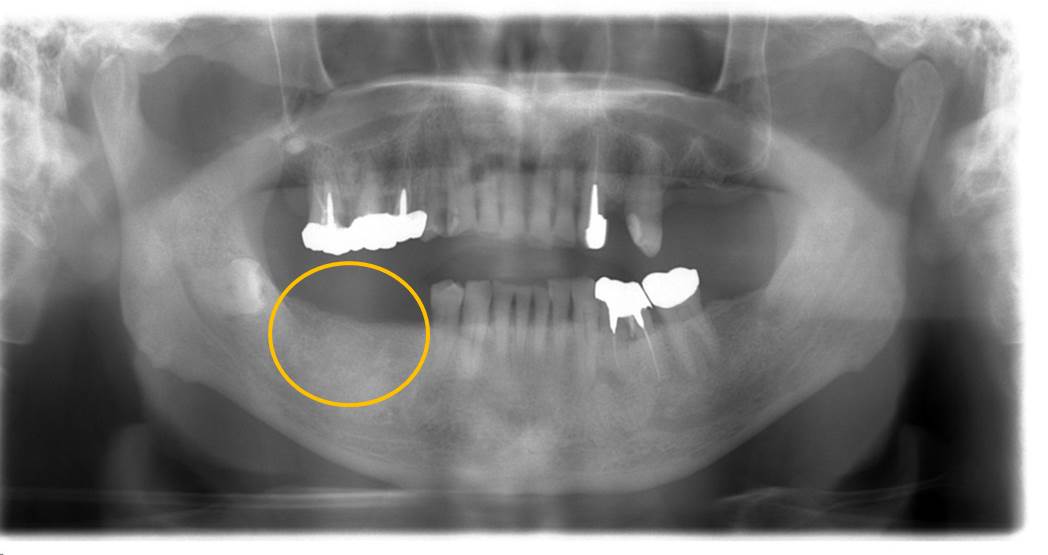

X線写真です。

インプラント埋入直後の写真です。